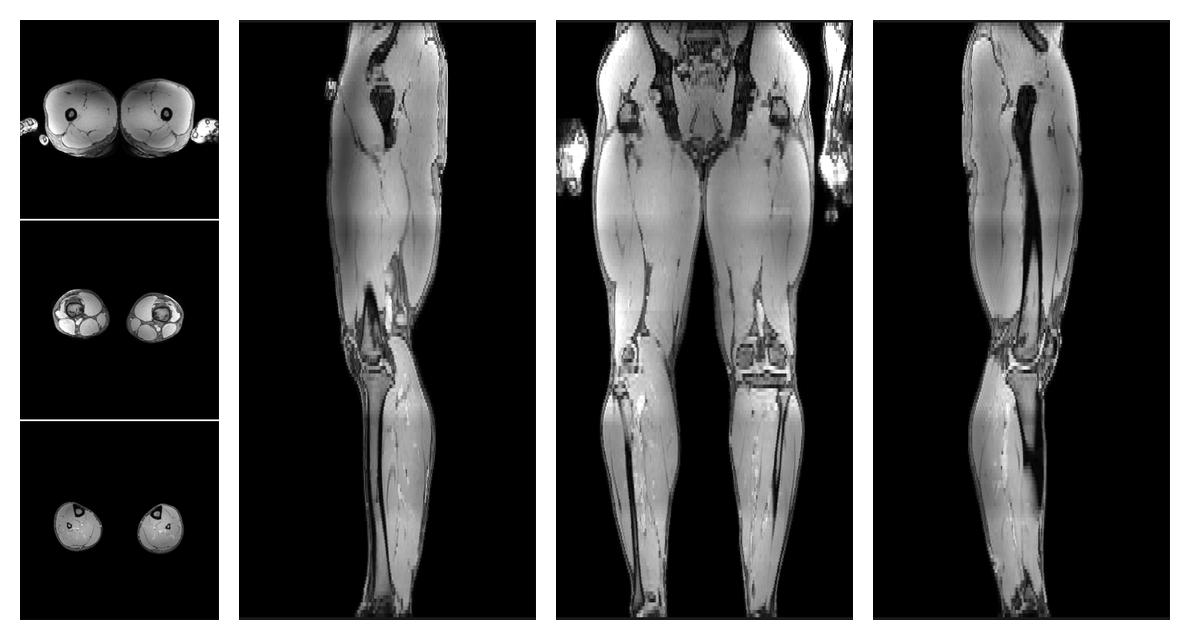

Water-fat quantification

Dixon based water fat quantification, for information look here».

• Out phase image

The out-phase image of the dixon reconstruction for water fat quantification.

• Fat fraction

The fat fraction of the lower extremity obtained from the dixon reconstruction for muscle water fat quantification.